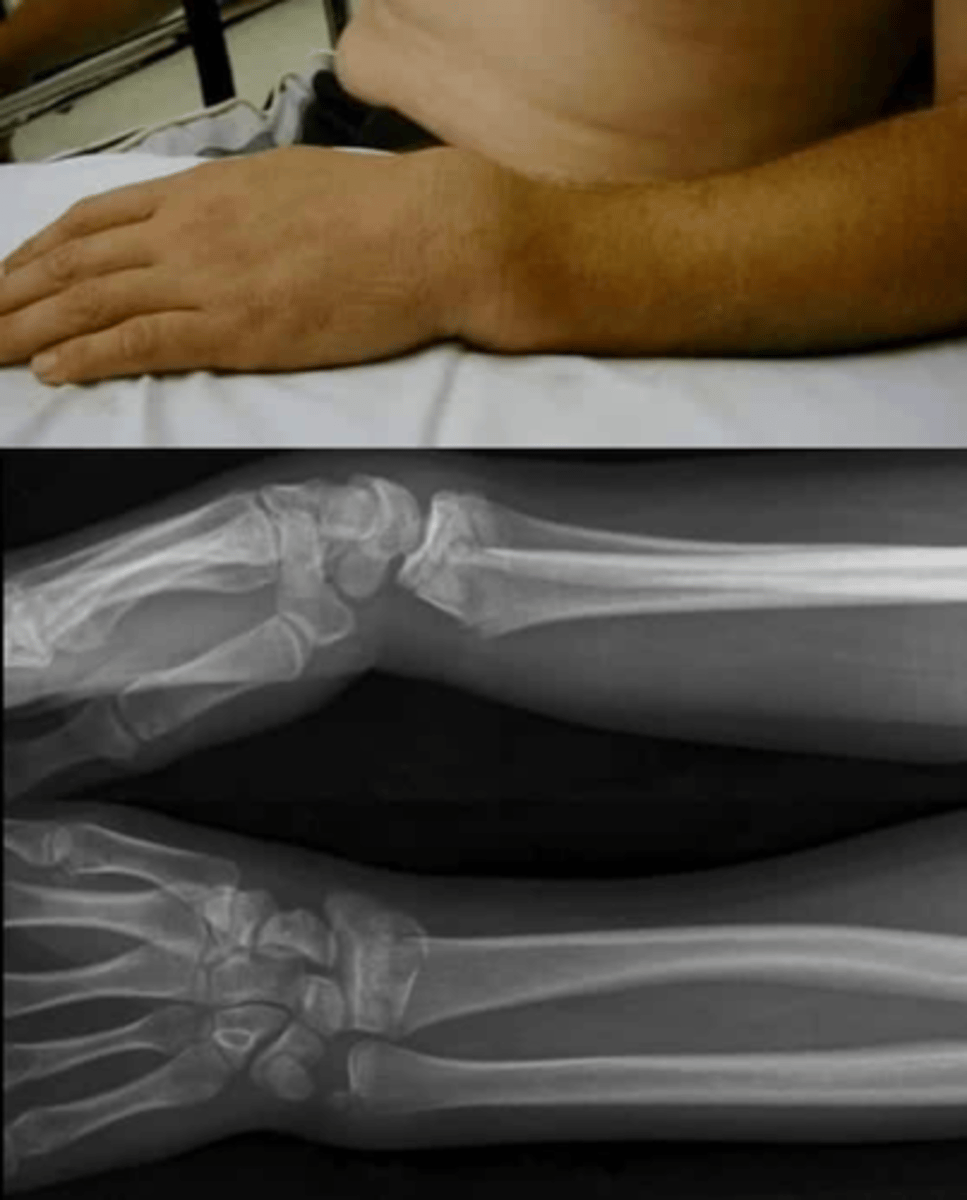

describe

FOOSH, distal radial fracture

what is this

distal radial fracture

distal portion of the distal bone pointing towards the dorsum (back) of the hand

Colles Fractures

colles fracture